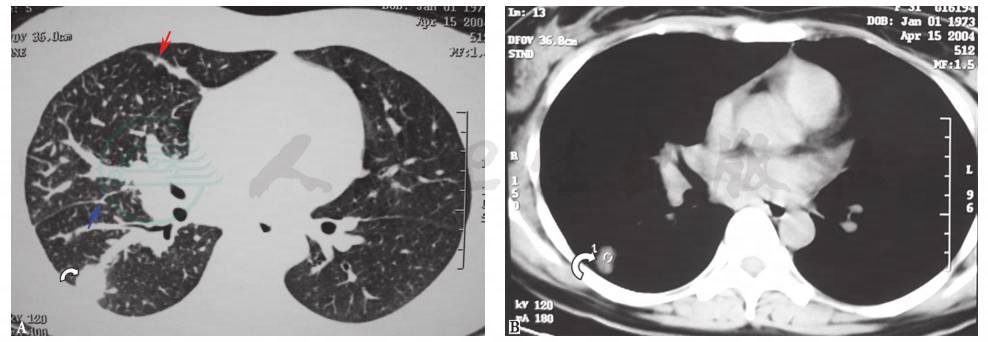

(2)肺淋巴管癌病(PLC)

指肿瘤在肺内沿淋巴管转移,影像学表现为肺部弥漫性沿淋巴管分布的结节及肺间质改变。PLC可来源于肺部肿瘤转移,此时可发现肺内原发肿瘤灶(图3);也可来源于肺外肿瘤转移,而在肺部不能发现明确的原发灶(图4)。本例患者除HRCT表现与PLC相似外,还合并纵隔淋巴结增大及胸腔积液,但肺、消化道、乳腺等部位均未发现明确原发灶,支气管肺泡灌洗液亦未找到肿瘤细胞,因此不能排除PLC,还需要更多的组织标本来进行病理诊断。

图3 肺淋巴管癌病胸部CT表现

肺窗示右肺下叶背段团块影(弧形箭头),伴右肺野内肺纹理增粗,右肺叶间裂增厚和结节样改变(蓝色箭头为斜裂,红色箭头为水平裂),并见小叶间隔及小叶内间隔增厚(A);纵隔窗示右下肺背段占位性病变(弧形箭头),未见肺门淋巴结肿大和胸腔积液(B)。病理诊断为肺淋巴管癌病

图4 肺淋巴管癌病胸部CT表现

女性患者,诊断为肺淋巴管癌病。胸部CT表现为双肺弥漫性小叶间隔增厚、叶间胸膜不规则增厚,未发现肺部原发肿瘤灶